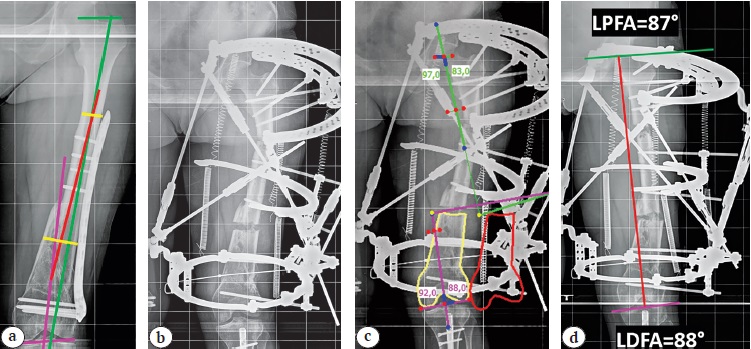

Рис. 1. Пружинная техника при коррекции двухвершинной деформации бедренной кости: а — планирование коррекции деформации с использованием анатомических осей (зеленым, красным и фиолетовым цветом отмечены оси фрагментов, желтым — уровни остеотомий); b — после наложения ортопедического гексапода и остеотомий; c — расчет в компьютерной программе (желтый контур — исходное положение мобильного фрагмента, красный — после коррекции); d — результат коррекции

Figure 1. The spring technique in correction of biapical femoral deformity: a — planning for deformity correction using anatomical axes (axes of the fragments are marked in green, red and purple, osteotomies levels — in yellow); b — after application of orthopedic hexapod and osteotomies; c — calculation in the computer program (a yellow contour indicates the initial position of the mobile fragment, a red one — after correction); d — the correction result